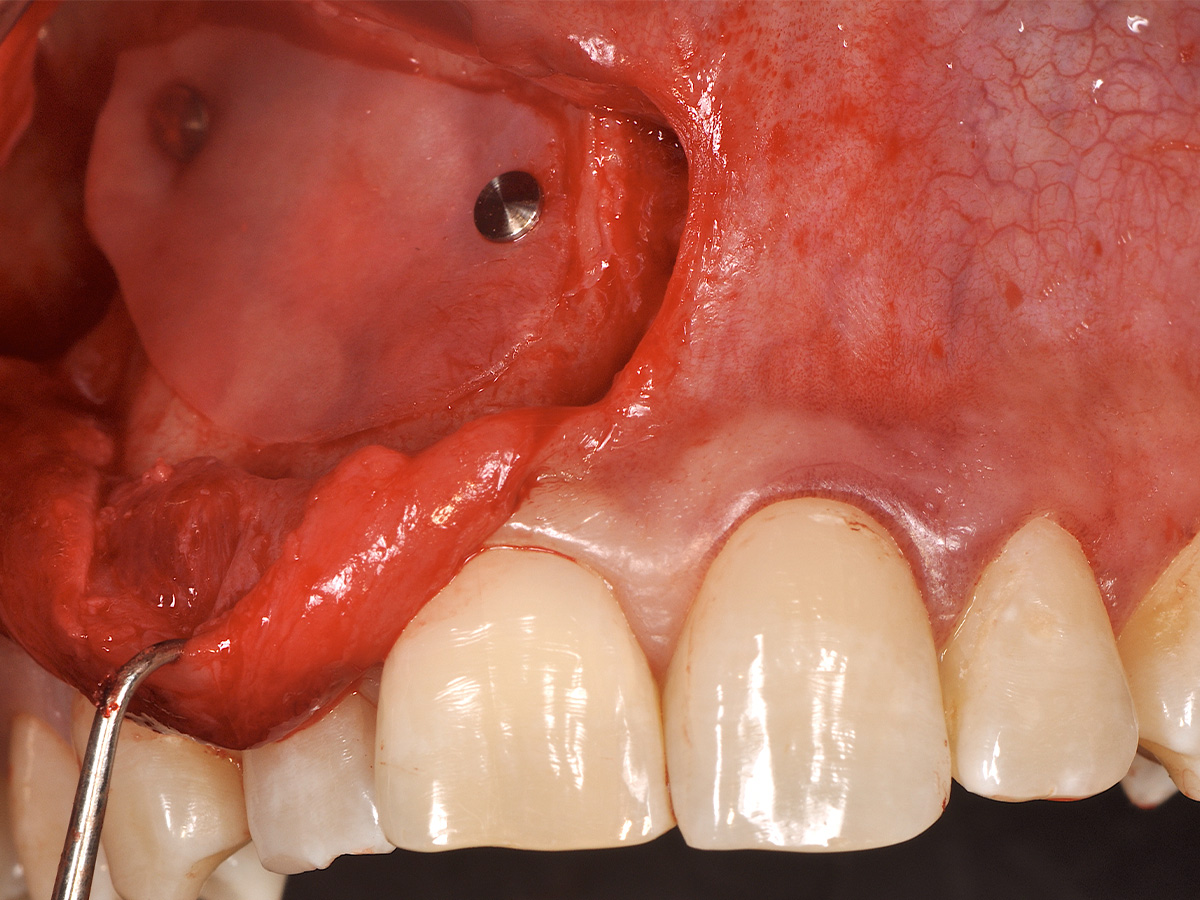

Abbildung 8

Die Schnittführung wurde aufgrund des bestehenden „Gummy Smile“ hoch im Vestibulum geführt...

Abbildung 9

...so konnte die delikate Parodontalstruktur in ihrer Form unangetastet belassen werden, um einen möglichst optimalen ästhetischen Erfolg zu erreichen.

Mit der Patientin wurde der Versuch des Zahnerhaltes trotz ausgedehnter Zyste besprochen. Gleichzeitig sollte das Zystenlumen zu einer sicheren ossären Durchbauung geführt werden, um eine implantologische Sofortversorgung vorzubereiten, falls zu einem späteren Zeitpunkt eine Zahnentfernung notwendig werden sollte. In der Phase vor der geplanten Operation wurden die Wurzelkanalfüllungen an Zahn 11 und 12 durch einen Endodontologen alio loco revidiert. Die Schnittführung wurde aufgrund des bestehenden „Gummy Smile“ hoch im Vestibulum geführt – so konnte die delikate Parodontalstruktur in ihrer Form unangetastet belassen werden, um einen möglichst optimalen ästhetischen Erfolg zu erreichen (Abb. 8, 9). Nach vestibulärer Freilegung wurde die Zyste vollständig entfernt und zur histopathologischen Untersuchung eingesandt (Abb. 10). Anschließend erfolgte eine Wurzelspitzenresektion an den Zähnen 11 und 12 durch die vestibuläre ossäre Perforation (Abb. 11), gefolgt von einer ultraschallbasierten, retrograden Kanalaufbereitung und Abdichtung mit MTA. Um die knöcherne Durchbauung am Boden der Zyste osteoinduktiv zu unterstützen, wurden mit Hilfe eines mechanischen Knochenschabers aus dem Bereich des rechten naso-palatinalen Pfeilers Knochenchips entnommen und als erste basale Augmentationsschicht in den ossären Defekt eingebracht (Abb. 12). Der größere Anteil von 80 % des Defektvolumens wurde mit einem vollständig resorbierbaren, xenogenen Augmentationsmaterial aufgefüllt (Abb. 13) (mp3®, OsteoBiol®). Der Defekt wurde zum Vestibulum hin mit einer stabilen, vollständig degradierbaren Membran abgedeckt (Abb. 14) (Soft Cortical Lamina, OsteoBiol®). Zum einen wurde hiermit im Sinne der GBR das Weichgewebe vom Augmentat getrennt. Zum anderen verhinderte die stabile Membran das Einwachsen eines Weichgewebeankers in den Defekt und damit eine narbige Verziehung im Vestibulum. Um eine Verschiebung der Membran zu vermeiden, wurde diese mit zwei Titanpins in der Kortikalis fixiert. Die Pins wurden bei Beschwerdefreiheit in situ belassen (Titan-Bone-Pin-System). Der Wundverschluss erfolgte einschichtig mit nicht resorbierbarem Nahtmaterial (Abb. 15) (Seralene® 5-0 DS-15). Peri- und postoperativ wurde eine antibiotische Abschirmung unter Fortführung für insgesamt drei Tage mit Amoxiclav 875/125 1-0-1 durchgeführt.